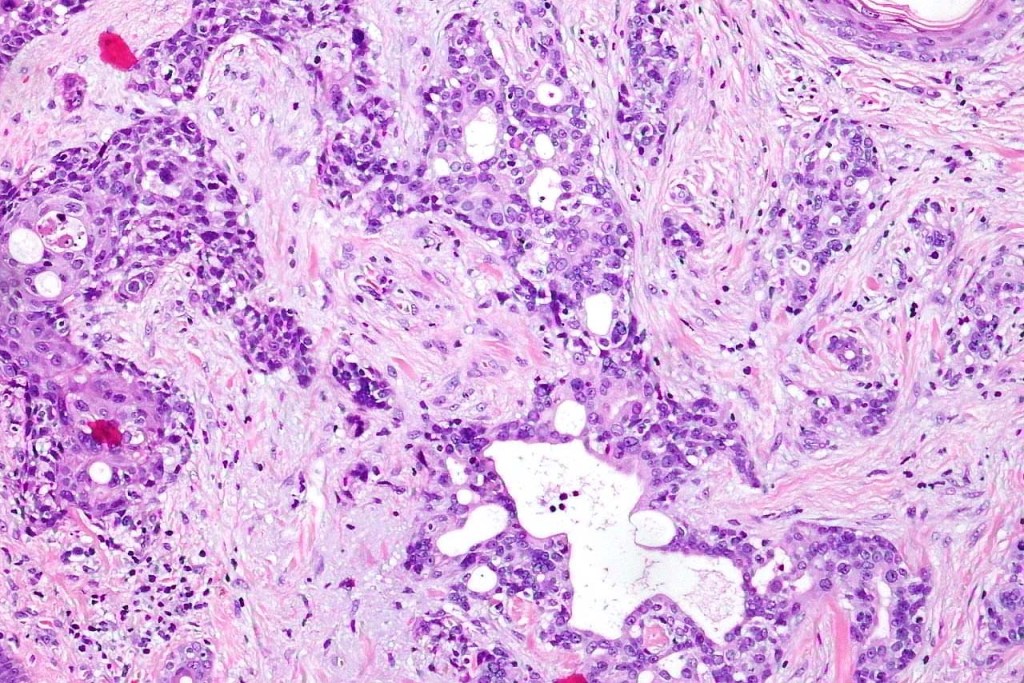

•Widely infiltrating biphasic tumor

•Adenocarcinoma in deeper reaches

•Variable pleomorphism and mitotic activity

•Deep part may show both ducts and glands

•Perineural infiltration is commonly seen